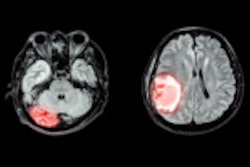

The causal relationship between BMI -- a modifiable factor associated with poor cardiovascular health -- and brain health is unclear, Lv's group noted. The team performed a study to explore the effect of BMI on neuroimaging features in adults of different ages and verify the causal relationship. It based the research on information from the KaiLuan study, which began in 2006 and consists of data from 681,275 individuals; this work included participants who visited the hospital at least three times and underwent brain MRI examination, with no evidence of dementia or mental disorders. Starting in 2020, patients received 3-tesla MR imaging for volumetric measurements of the brain structure, white-matter hyperintensity, and skeletonized white-matter tract at the voxel level.

Lv's and colleagues' study included data from 1,074 adults between the ages of 25 and 83. Overall, they found that high BMI was associated with a wide range of negative brain health effects. They also reported the following:

- Differences in cerebral parenchyma volume between those adults under 45 years of age with a BMI > 26.2 kg/m2 corresponded to 12 years of brain aging compared to those with a normal BMI.

- Differences in white matter hyperintensities were statistically significant for participants over the age of 60 with a high BMI, with a 6-ml larger volume.